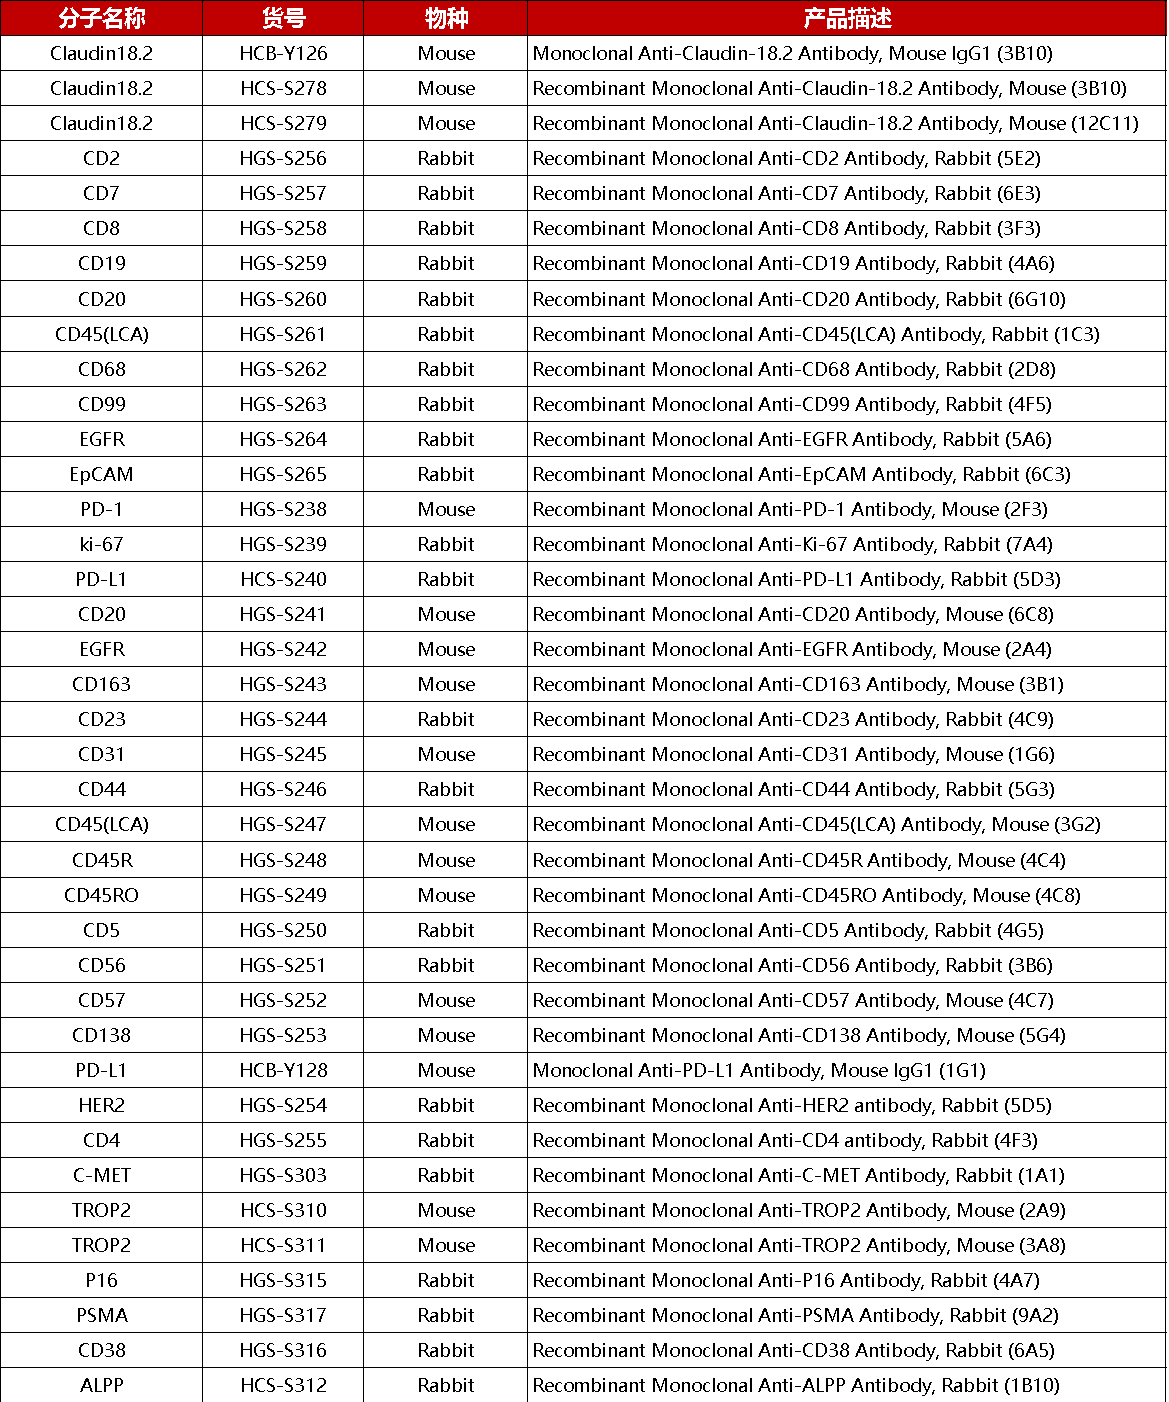

产品列表

TROP2免疫组化抗体产品列表,点击列表即可查看产品详情

更多IHC免疫组化抗体产品

免疫组化抗体产品列表,点击列表即可查看产品详情

免疫组化抗体产品列表